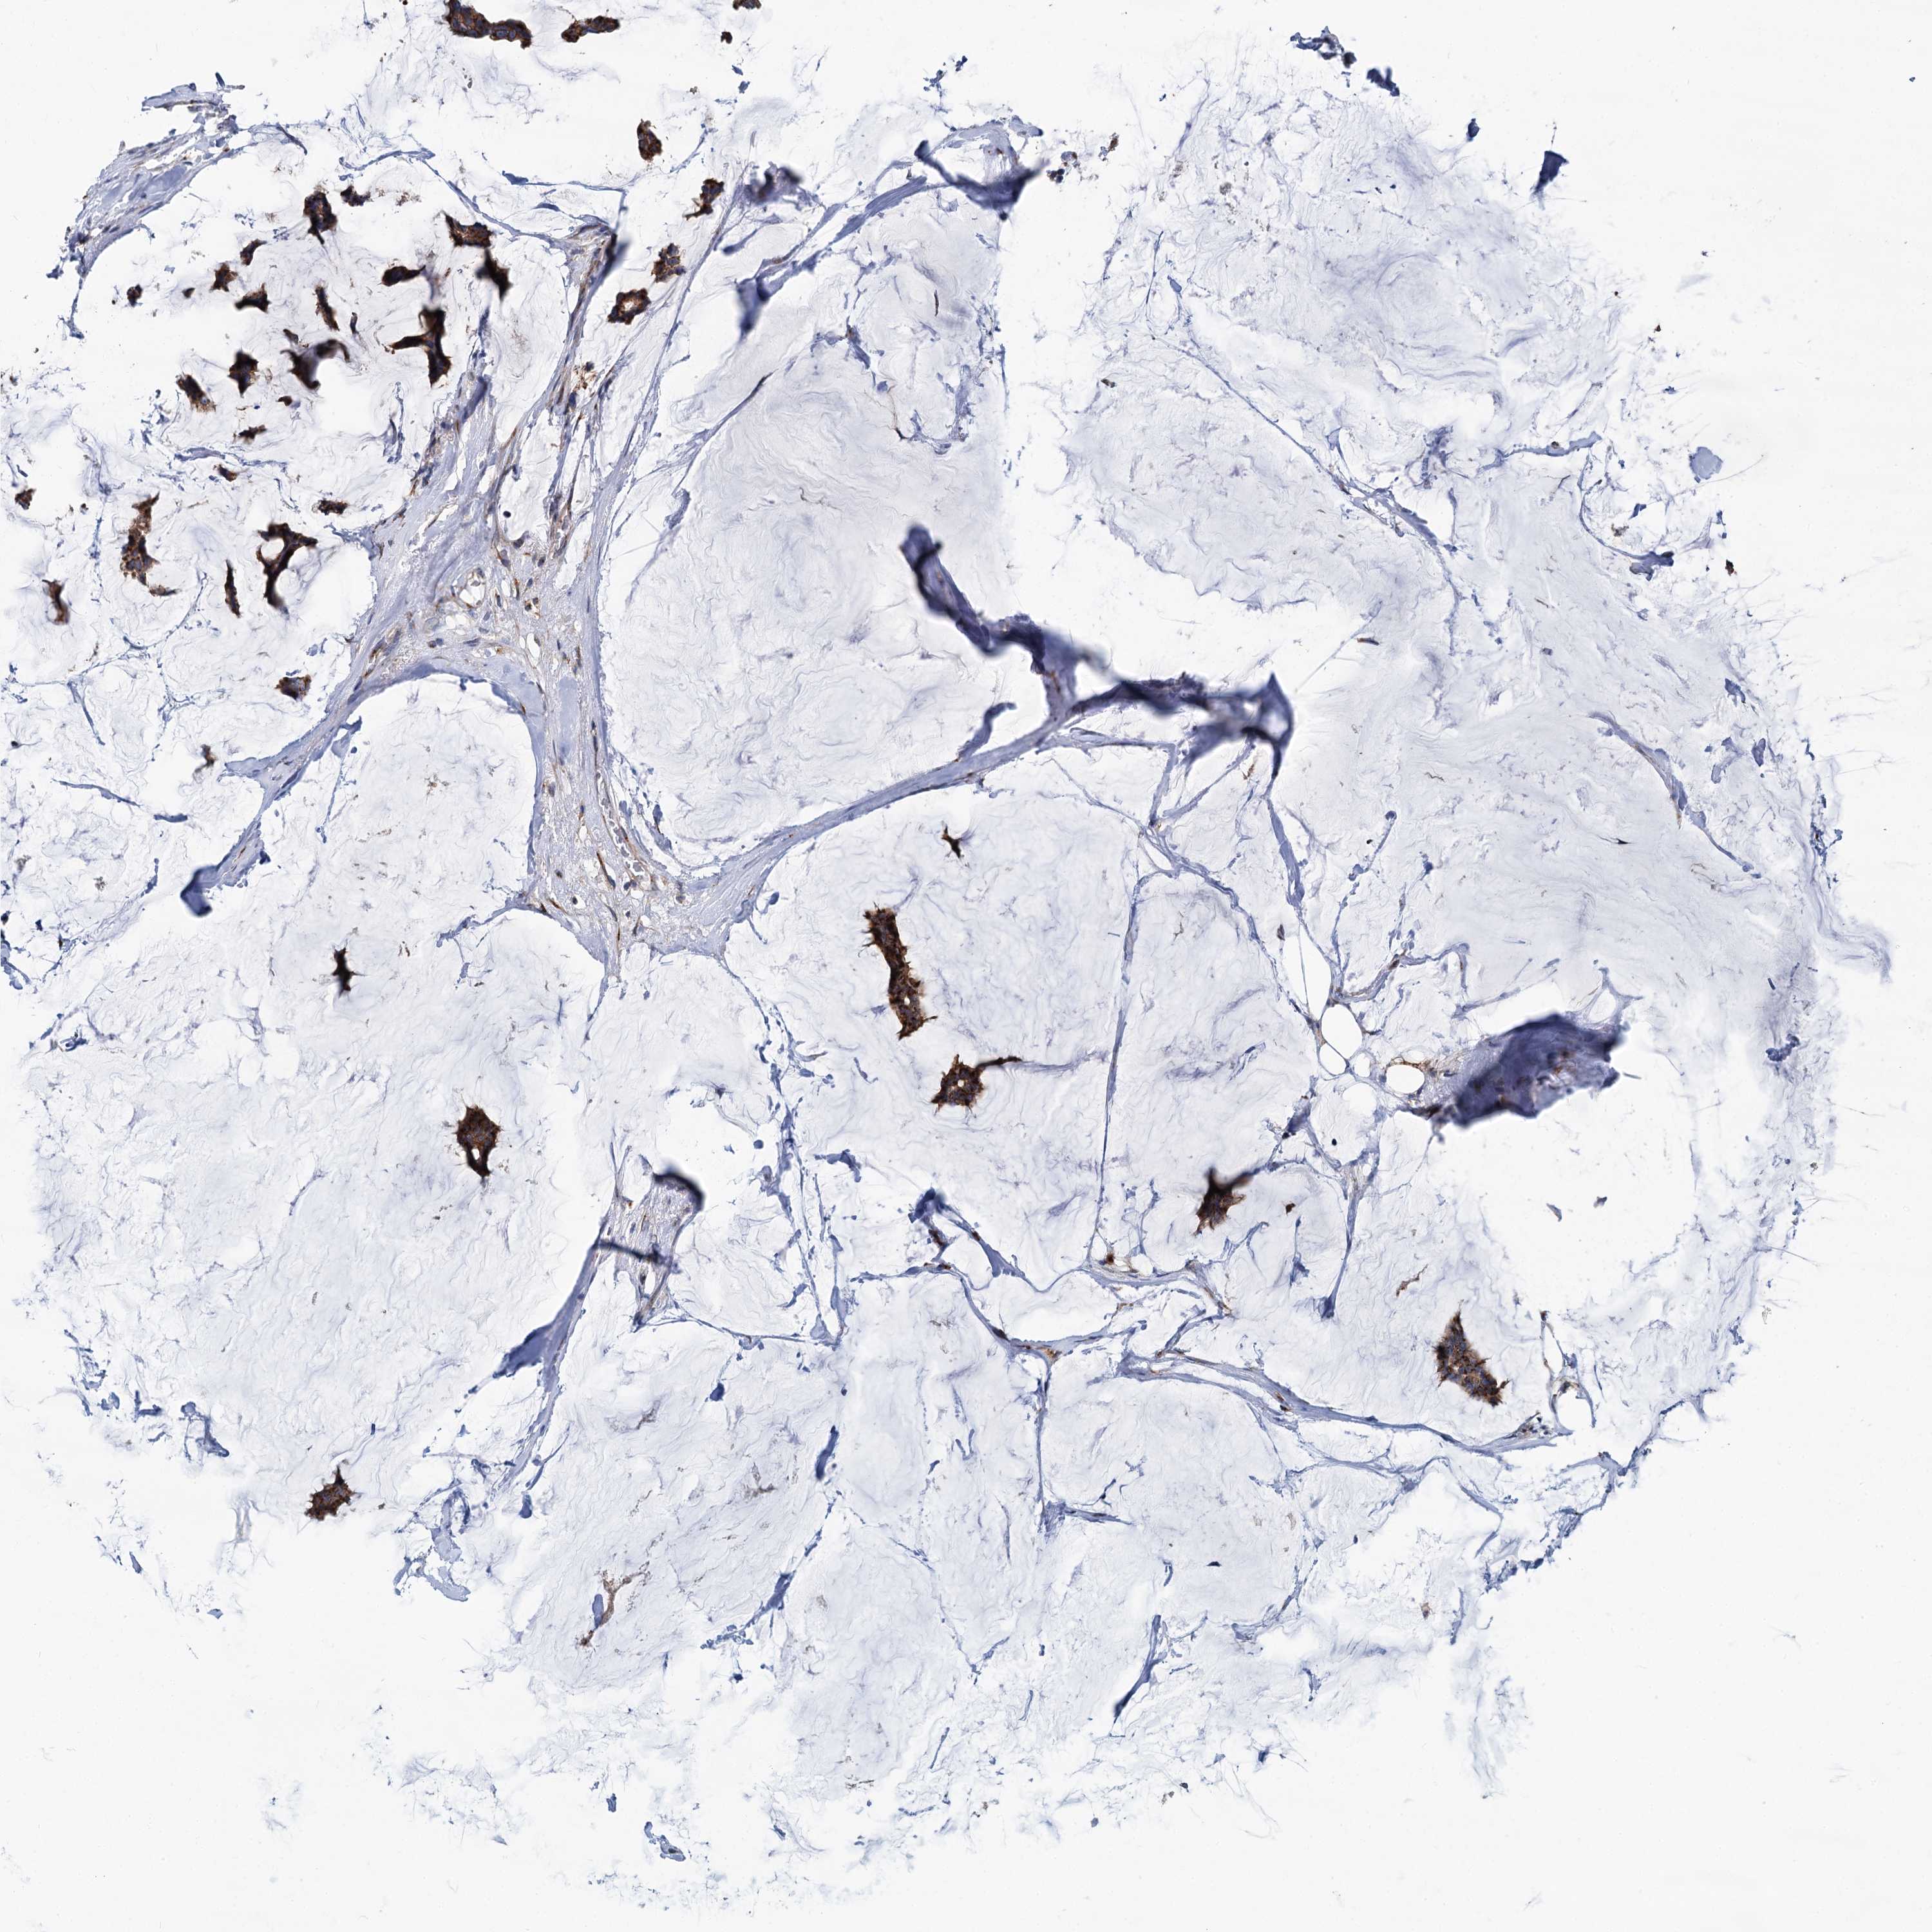

BRCA TCGA BRCA VALIDATION PROTEIN EXPRESSION